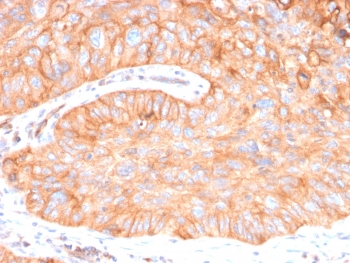

IHC staining of FFPE human prostate carcinoma with CD73 antibody (clone NT5E/2545). HIER: boil tissue sections in pH9 10mM Tris with 1mM EDTA for 10-20 min and allow to cool before testing.

IHC staining of FFPE human pancreatic carcinoma with CD73 antibody (clone NT5E/2545). HIER: boil tissue sections in pH9 10mM Tris with 1mM EDTA for 10-20 min and allow to cool before testing.

IHC staining of FFPE human colon carcinoma with CD73 antibody (clone NT5E/2545). HIER: boil tissue sections in pH9 10mM Tris with 1mM EDTA for 10-20 min and allow to cool before testing.